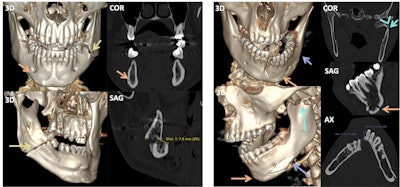

The images on the left side of the white vertical bar show a bilateral, simple, and nondisplaced nasal fracture. The nasofrontal suture (orange arrows), nasal septum (green arrow), and anterior nasal spine (yellow circles) remain intact, while the fracture line crosses the left nasomaxillary suture (red arrows). On the other hand, the image on the right contains a bilateral, comminuted, and displaced nasoseptal fracture (red circle), in which the nasal septum is also involved (red arrow).